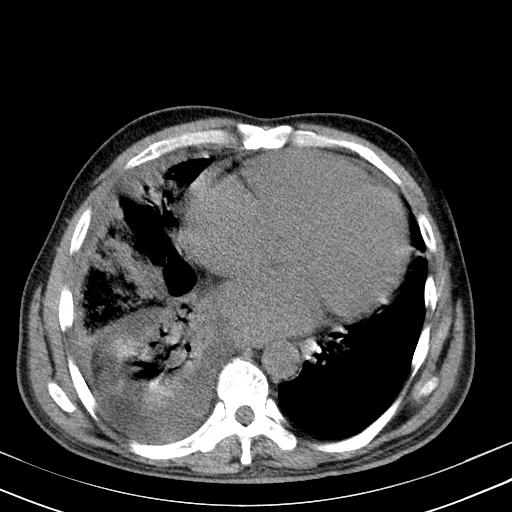

以下是引用zxl51642在2010-3-21 17:06:00的发言:[br]右下中心型肺癌并阻塞性肺炎/不张,纵膈淋巴结肿大,右侧大量胸腔积液,左侧少量胸腔积液,少量腹水。建议纤维支气管镜进一步检查。